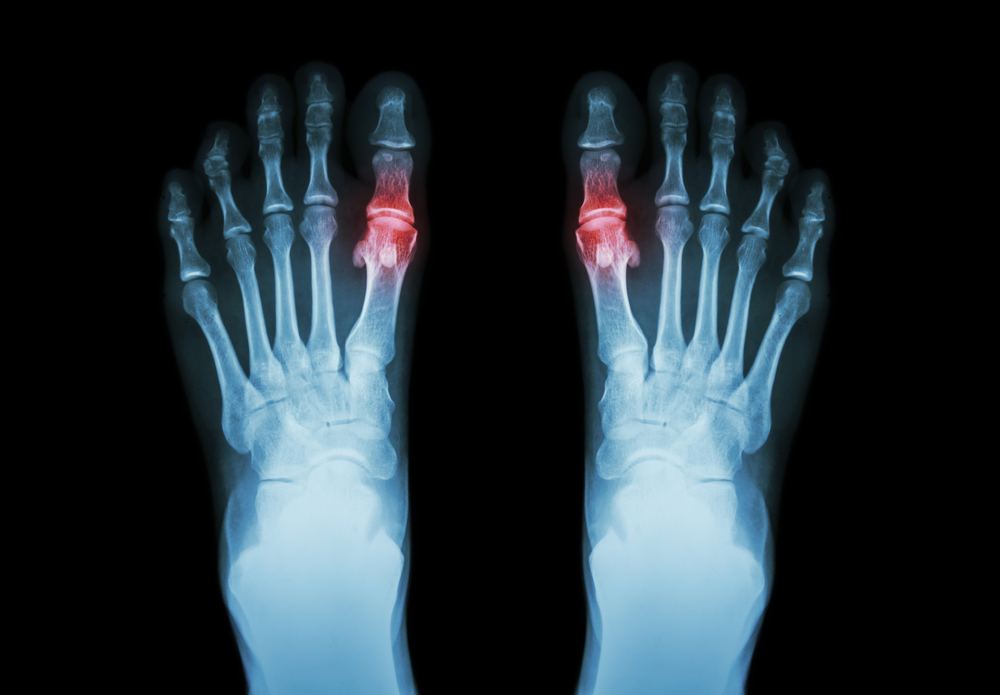

Подагра – это болезнь, которая является разновидностью воспаления суставов и вызывается нарушением обмена веществ. Этот недуг сопровождается отложением солей уратов (соли мочевой кислоты) на различных тканях.

- Появление острого подагрического артрита и поражение почек.

Накопление уратов происходит в виде отложения кристаллов игольчатой формы в бессосудистых тканях, т. е. в хрящах, связках, сухожилиях, периферических суставах и зонах, которые подвергаются наибольшему трению или охлаждению (локти, седалищные бугры и ушные раковины). При продолжительном течении подагры соли начинают накапливаться в более крупных суставах.

Пусковым механизмом приступа подагрического артрита становится срабатывание «сторожевой полисистемы» полиморфно-ядерных лейкоцитов (в большей мере нейтрофилов) и плазмы крови на кристаллические отложения уратов. Взаимодействие этих факторов крови и солей мочевой кислоты приводит к образованию медиаторов воспаления и простагландинов. Это провоцирует воспаление в суставных и мягких тканях, которое проявляется симптомами артрита.